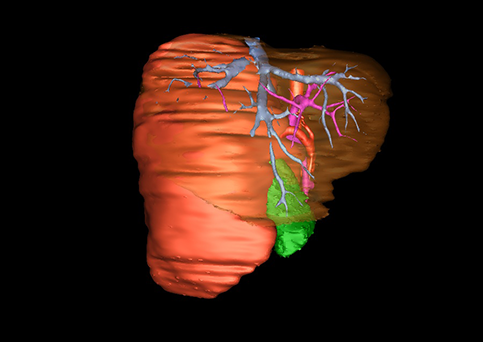

图1 位于肝右的叶肝母细胞瘤, 6个月,男婴

目前常用的检查方法有B超检查、CT、MRI、血管造影等。与其它的腹部肿块的诊断不同,对于小儿肝母细胞瘤血管造影具有重要的意义,可以作为手术前介入治疗的手段,也可为手术提供非常有效的影像学指导,但技术要求高,操作较复杂,且给患儿带来一定的痛苦。近年借助计算机辅助手术系统进行CT原始影像三维重建、手术规划和计算机虚拟手术技术,为精准肝脏手术提供了极为有效的技术支持。

近年来由于数字医学的发展,基于可视化三维重建技术的计算机辅助手术系统极大推进了小儿肝脏肿瘤的精准手术的进步。可以立体透视肝脏解剖、精确掌握肝段的边界、精确测算肝段乃至任意血管所支配的功能体积、准确定位病灶及其与邻近血管的解剖关系,最终对不同手术方案进行比较、筛选和优化。因此,计算机辅助手术规划系统是实现精准肝切除的有力辅助工具,是未来数字外科、精准外科等21世纪外科新理念的重要技术支撑。

计算机辅助手术规划系统具有良好的操作可行性、计算准确性和三维显示效果,可半透明、交互式显示真实的肝内立体解剖关系和空间管道变异,准确计算肝内管道的直径、走行角度,两点间的垂直距离,和任意血管的支配或引流范围等传统二维影像无法获取的信息,有助于实施个体化手术,提高了手术的确定性、预见性和可控性。计算机辅助手术规划系统可直观显示预留肝脏的结构和功能,并可通过虚拟切割功能辅助术者对手术方案进行蹄选和优化,系统评估手术风险和制定对策,改变了部分二维规划的术式和切除范围,使部分二维规划认为不能切除的患者成功手术,提高了手术的根治性、安全性和病变的可切除性,更加符合精准肝脏外科的术前规划要求。详见第11章。